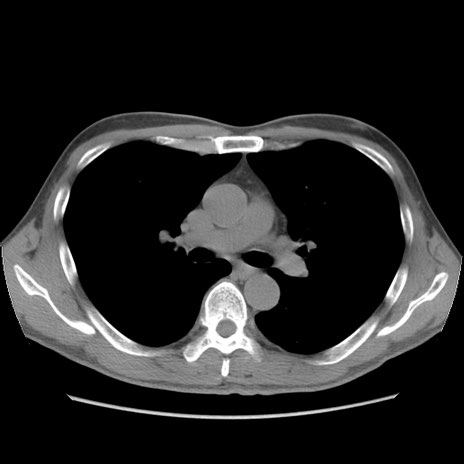

症例56 CT(横断像)

脂肪ウインドウ